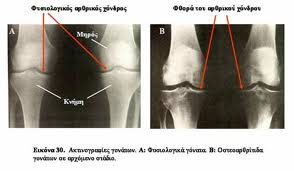

Ο ορθοπεδικός ιατρός θα θέσει τη διάγνωση με βάση τα ανωτέρω και την κλινική εξέταση. Οι απλές ακτινογραφίες βοηθούν στην επιβεβαίωση της διάγνωσης καθώς διακρίνεται η μείωση του μεσοδιαστήματος μεταξύ των οστών εξαιτίας της καταστροφής των χόνδρων καθώς και η τυχόν παρουσία οστεοφύτων. Οι εξετάσεις αίματος χρησιμεύουν στον αποκλεισμό αυτοάνοσης αρθρίτιδας.